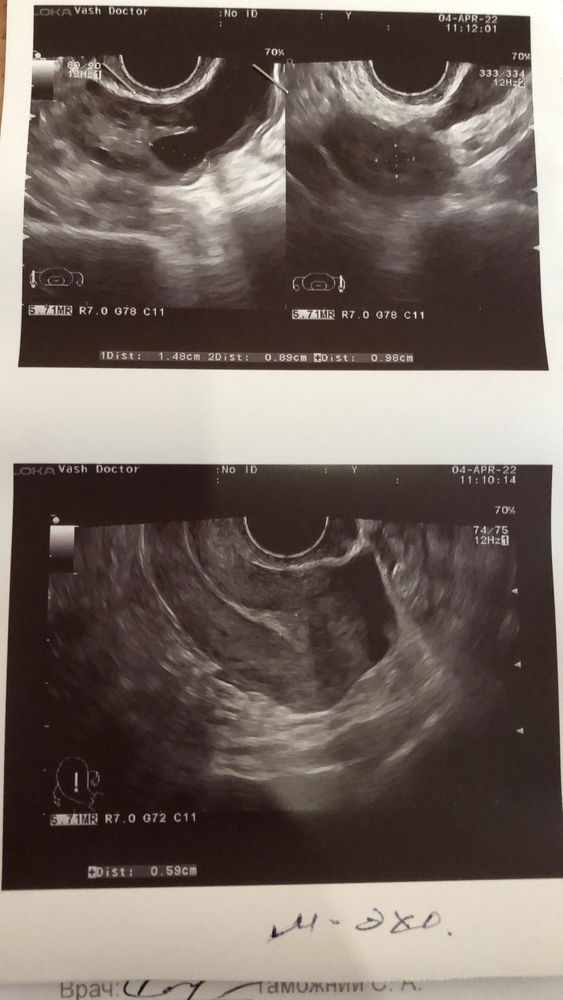

Ну что, О в ЛЯ это конечно здорово, ну как вот эндик с 6,4 мм ушёл в 5,9😭😭😭😭😭😭😭😭😭я хочу рыдать… и укол как то неохотно уходит🙄